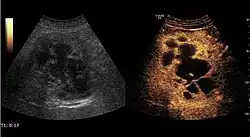

Hydatid liver cyst. Diagnostic criteria are the presence of membranes and sediment inside.